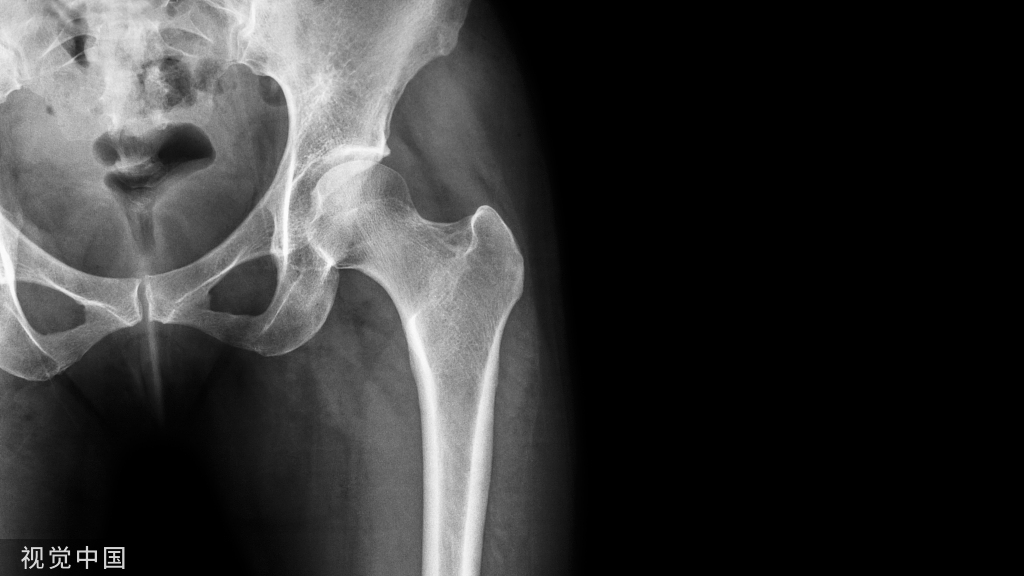

- 复位效果依靠术中影像学结果评判,包括X线正位片,侧位片,斜位片及Canale片。

▲ 侧位片检查

- 如果没有术中C形臂,则可用多角度X线平片来代替。

- 最后再行X线检查,确认精确复位和固定物的位置。